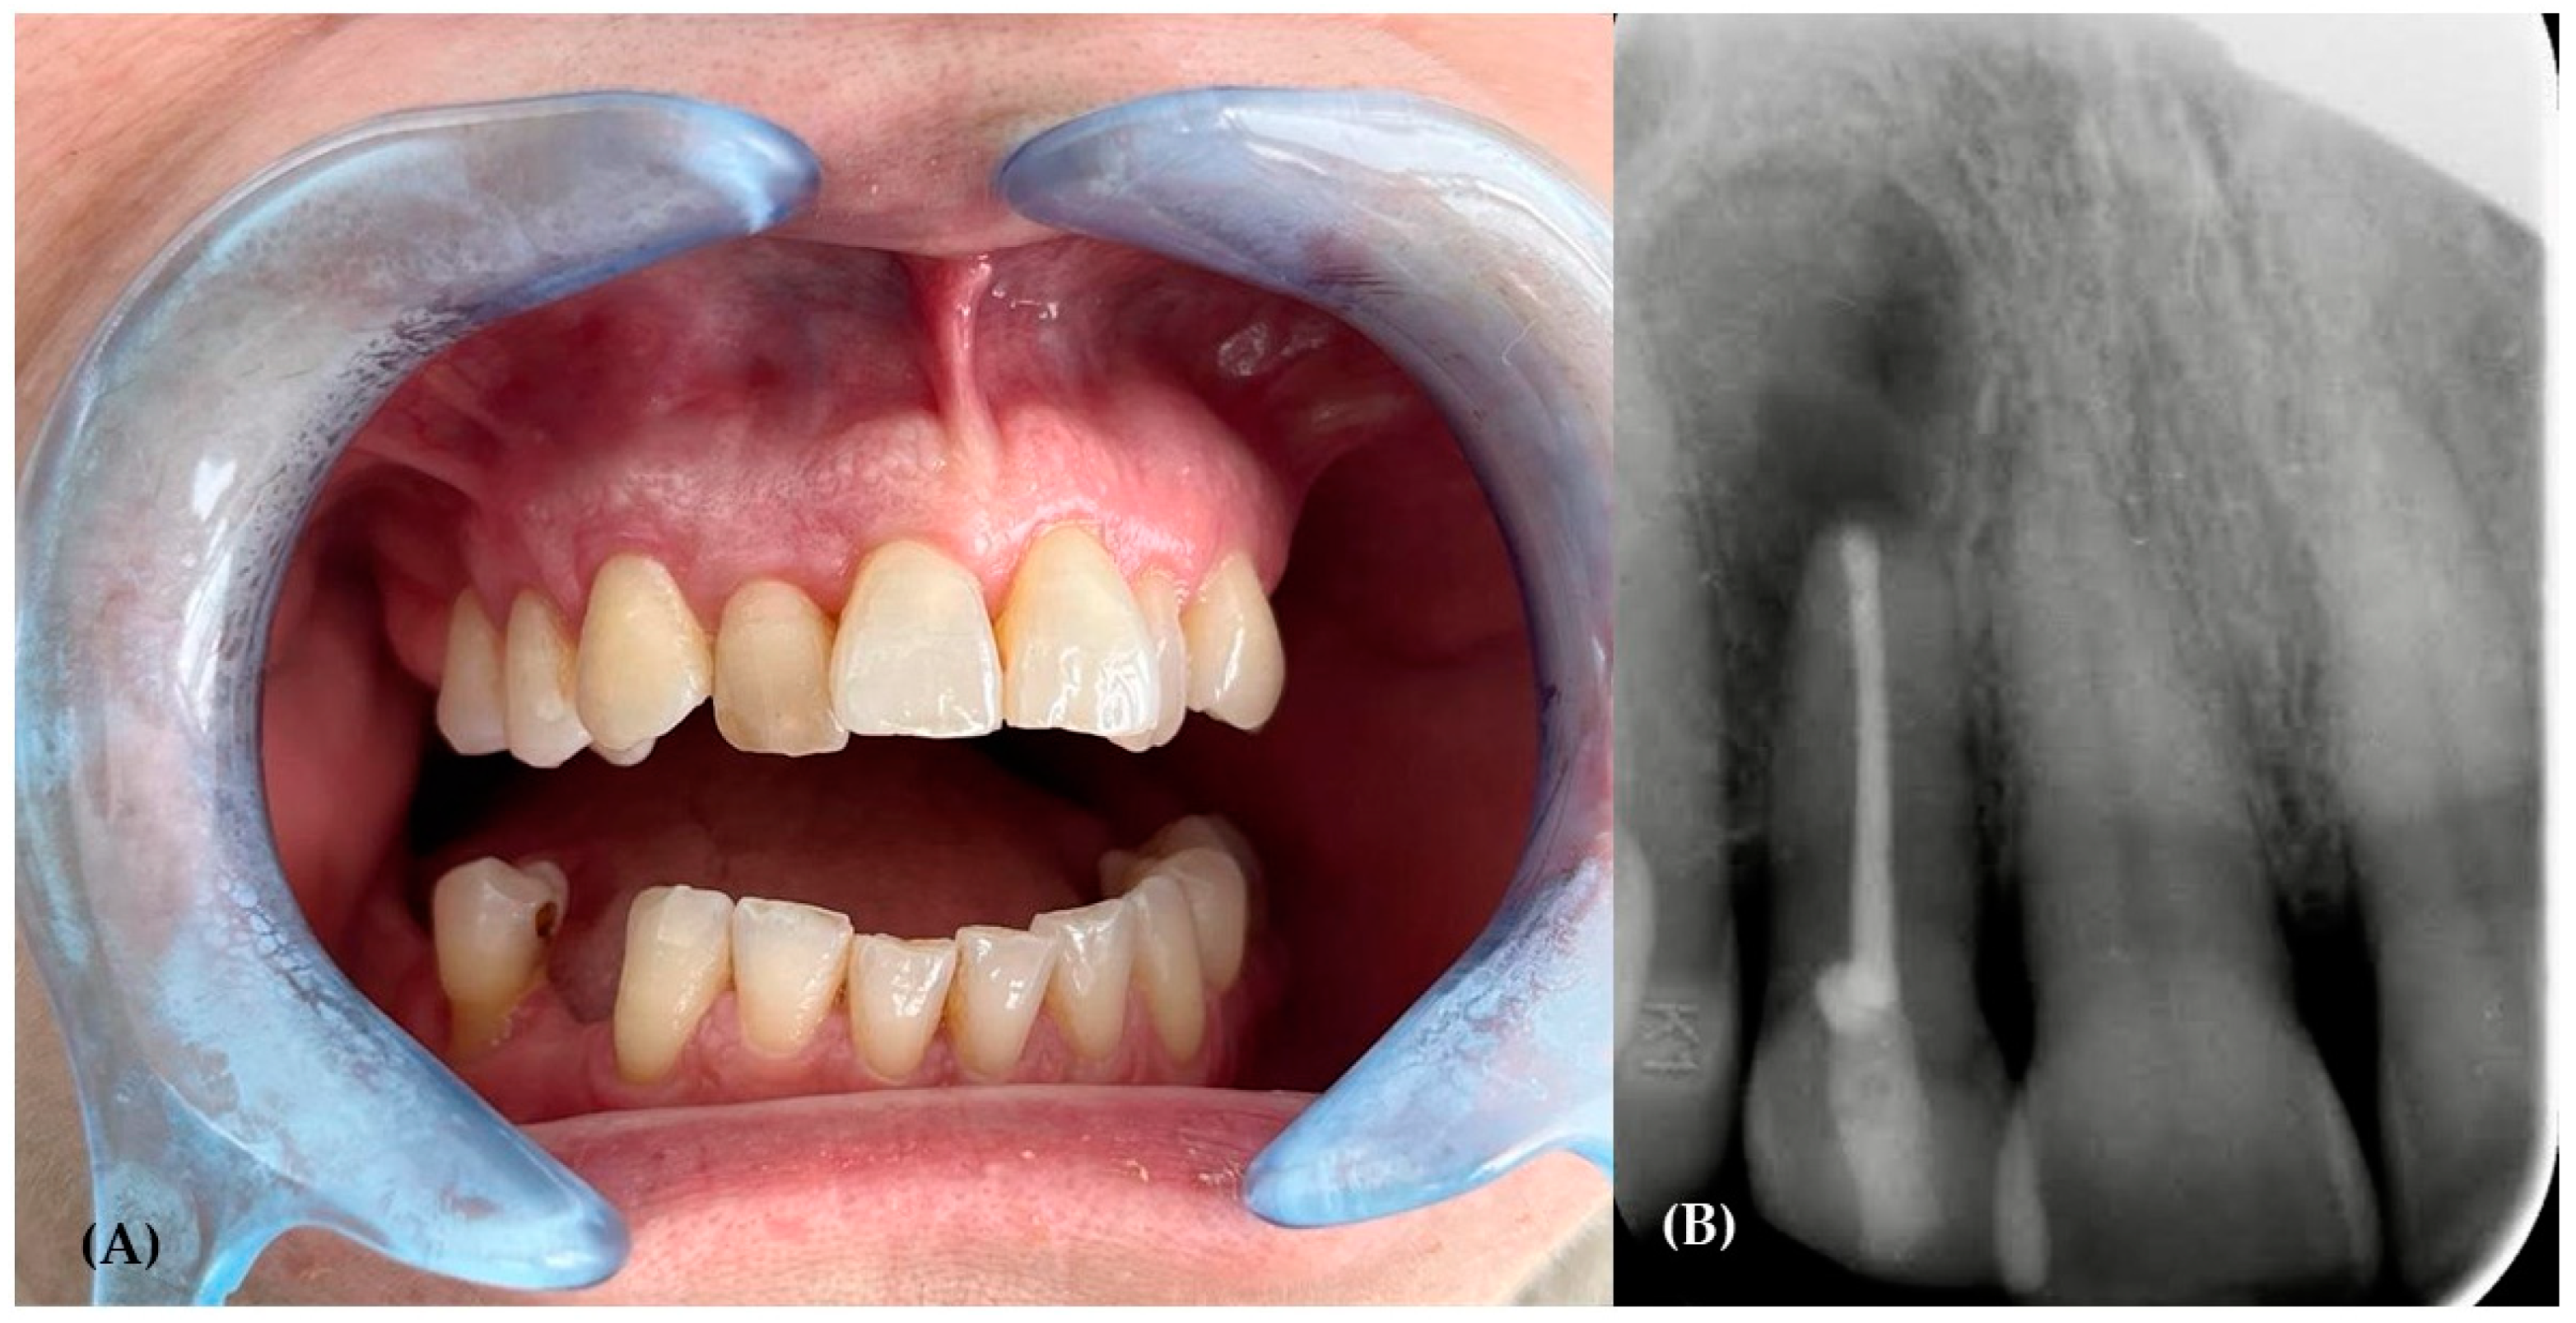

2. The Case